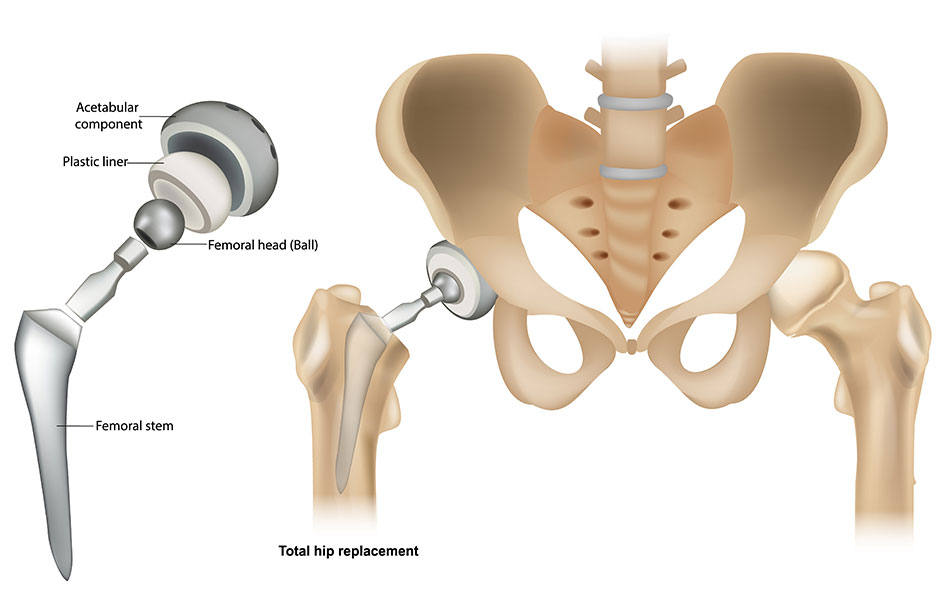

Total Hip Replacement Surgery Anatomical Acetabular Stock Vector

https://image.shutterstock.com/z/stock-vector-total-hip-replacement-surgery-with-anatomical-acetabular-prosthesis-outline-diagram-labeled-2117327951.jpg

What Is A Joint Replacement Elite Sports Medicine Orthopedics

Total Hip Replacement BJISG

Total Hip Replacement Hip Osteoarthritis